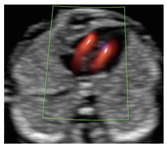

Figure 1.

Case of disagreement in the characterization of color Doppler pattern on the 3VTV between operators 1 and 2 in a case of Ebstein anomaly at 12 + 6 weeks’ gestation. (A,B) show different frames of a videoclip of the 3VTV. (A) Operator 1 observed an abnormal 3VTV pattern in terms of “abnormal vessel number”; (B) operator 2 characterized the same case as with “abnormal vessel dimensions”. AoA, aortich arch; T, trachea; arrow, small pulmonary artery.